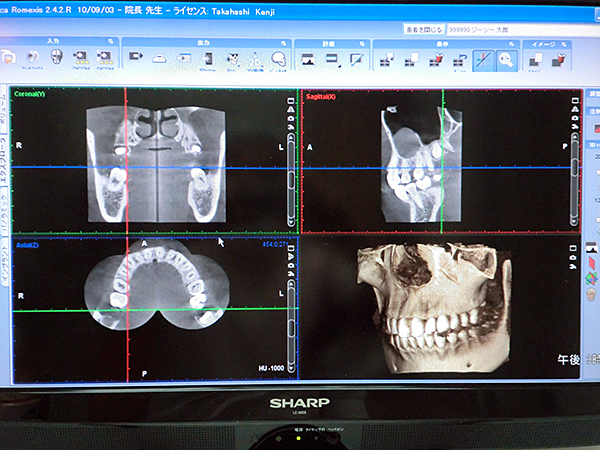

CTスキャン画像

インプラント治療の必需品ですが、ちょっと気持ち悪いですね。